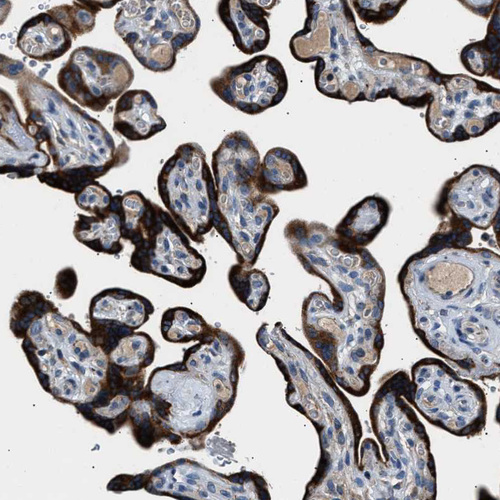

Immunohistochemical staining of human placenta shows strong cytoplasmic positivity in trophoblastic cells.